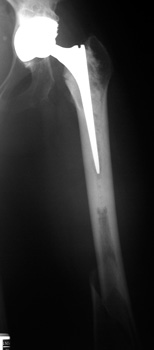

Fracture distal to femoral stem

Stress riser distal to prosthetic